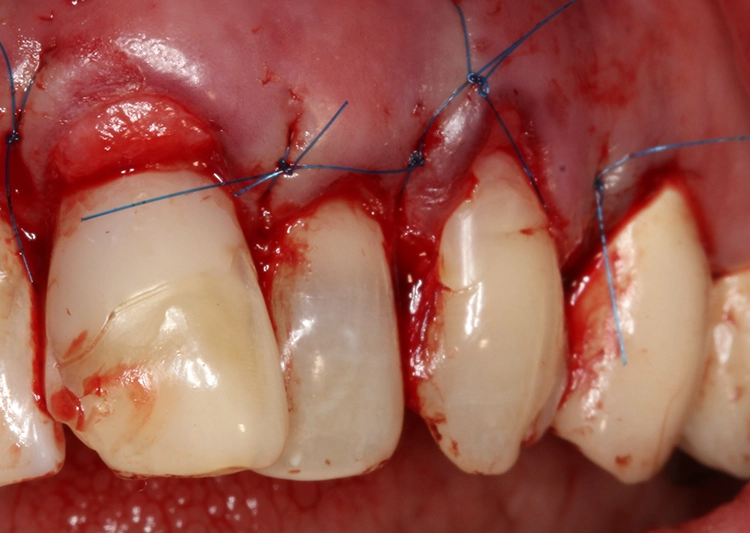

So sollte an den Zähnen 21 und 23 eine Rezessionsdeckung mit Verdickung des Gewebes und an Zahn 22 eine chirurgische Kronenverlängerung durch Exzision der Gingiva ohne Osteotomie erfolgen (Low-Crest-Typ). Der Verlauf der Schneidekantenlängen und die Zahnstellung sollten in einem 2. Schritt durch Vollkeramikteilkronen bzw. Veneers mit Inzisalfassung harmonisiert werden. In der Behandlungsplanung dieses Falles kam erschwerend hinzu, dass 3 verschiedene parodontalchirurgische Behandlungsindikationen zusammenkamen:

Bei Patienten vom Low-Crest-Typ beträgt der Abstand zwischen Gingivarand und Knochen vestibulär mindestens 3 mm, interproximal mindestens 5. Daher führt bei diesen Patienten unter Umständen eine einfache Exzision von Gingiva ohne Knochenchirurgie bereits zu einem zufriedenstellenden Ergebnis.

Behandler- und fallspezifische Unterschiede in der Operationstechnik sind die Regel, Einigkeit besteht allerdings in einer minimalinvasiven Herangehensweise. So wird beispielsweise versucht, wenn möglich auf Entlastungsinzisionen zu verzichten [5,12,28,30]. Die Patientin willigte dann in die geplante Therapiemaßnahme ein; diese bestand aus präprothetischer parodontalchirurgischer Rezessionsdeckung mittels Bindegewebetransplantat, chirurgischer Kronenverlängerung und zeitversetzter restaurativer Therapie mit Vollkeramikteilkronen bzw. Veneers mit Inzisalfassung.

Postoperativ wurde die Patientin angewiesen, für 2 Wochen mit Chlorhexamed zu spülen. Außerdem wurde ihr ein ausdrückliches Putzverbot im Operationsgebiet und die Vermeidung jeglicher mechanischen Irritationen verordnet. Die Nähte am Gaumen (Abb. 6) konnten bereits nach 1 Woche entfernt werden, wohingegen die Nähte am Transplantat erst nach 14 Tagen entfernt wurden. Ab diesem Zeitpunkt konnte die Patientin wieder sehr vorsichtig mit einer sehr weichen Zahnbürste putzen (Abb. 7).